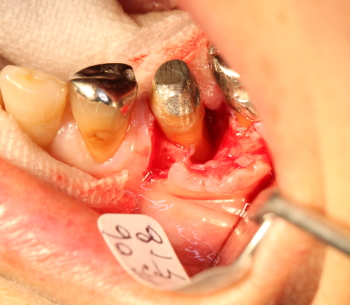

同部を剥離、掻爬

骨補填剤を充填。

縫合

術後約3.5カ月後

予後良好